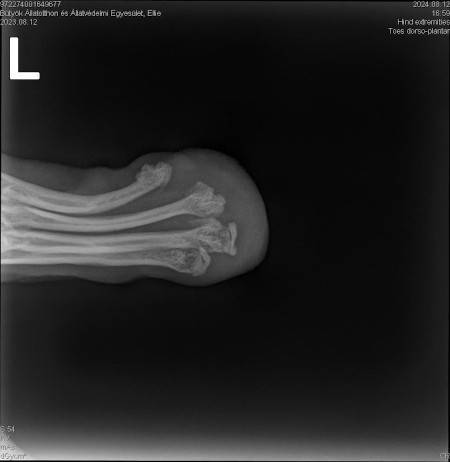

Ellie ist ca. 1 Jahr alt (Stand 08/2024) und hat bereits eine bewegte Vergangenheit hinter sich. Nach 5 Tagen intensiver Versuche konnte sie endlich von der Strasse gerettet werden, wo sie hungrig, durstig und in einem schlechten gesundheitlichen Zustand allein und orientierungslos umherirrte. Elli war von Flöhen und Zecken geplagt und stark abgemagert, doch trotz all dieser Herausforderungen zeigt sie einen unglaublichen Lebenswillen. Elli hat ein Handicap: Ihr fehlt ein Fuß am Hinterbein. Ob dies auf einen Unfall oder eine angeborene Fehlbildung zurückzuführen ist, wissen wir nicht. Doch Elli lässt sich davon nicht einschränken! Sie zeigt sich flink und steckt voller Energie. Ellie kommt erstaunlich gut mit ihrem Bein zurecht, es stört sie in keiner Weise und sie kann problemlos laufen, spielen und sogar rennen. Dennoch benötigt sie einen Schutz für ihren Stummel, entweder eine passende Prothese oder einen gefütterten Silikonschuh. Dies sollte in ihrem neuen Zuhause gründlich tierärztlich abgeklärt werden. Trotz ihrer Vergangenheit ist Elli eine unglaublich liebe, verschmuste und fröhliche Hündin. Sie liebt die Nähe zu Menschen, ist sehr anhänglich und versteht sich gut mit anderen Hunden. Ihre neuen Menschen sollten Freude daran haben, ihr alles ruhig und geduldig beizubringen, was so ein junges Mädel für ihr weiteres Leben als Familienhündin wissen muss. Ebenso sollten sich die neuen Besitzer bewusst sein, dass ein Hund nicht nur Freude, sondern auch jede Menge Arbeit und Verantwortung mit sich bringt, damit Ellie sich zu einer tollen Begleiterin entwickeln kann. Für unsere Herzensbrecherin suchen wir ein liebevolles, fürsorgliches und dauerhaftes Zuhause, wo sie nebst viel Spass auch abwechslungsreiche Spaziergänge erleben darf, wo sie artgerecht ausgelastet wird und täglich die Zuwendung und Pflege bekommt die sie verdient. Wer erfüllt den Traum von unserer Zuckerschnute Ellie und gibt ihr trotz ihres kleinen Handicaps die Chance ein treues Familienmitglied zu werden?